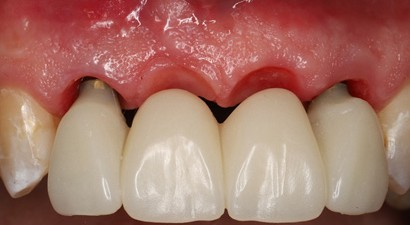

The 6 weeks follow up showed stable soft tissue, no signs of inflammation, and good maintenance by the patient. The implants showed no mobility and appeared to be integrating uneventfully.